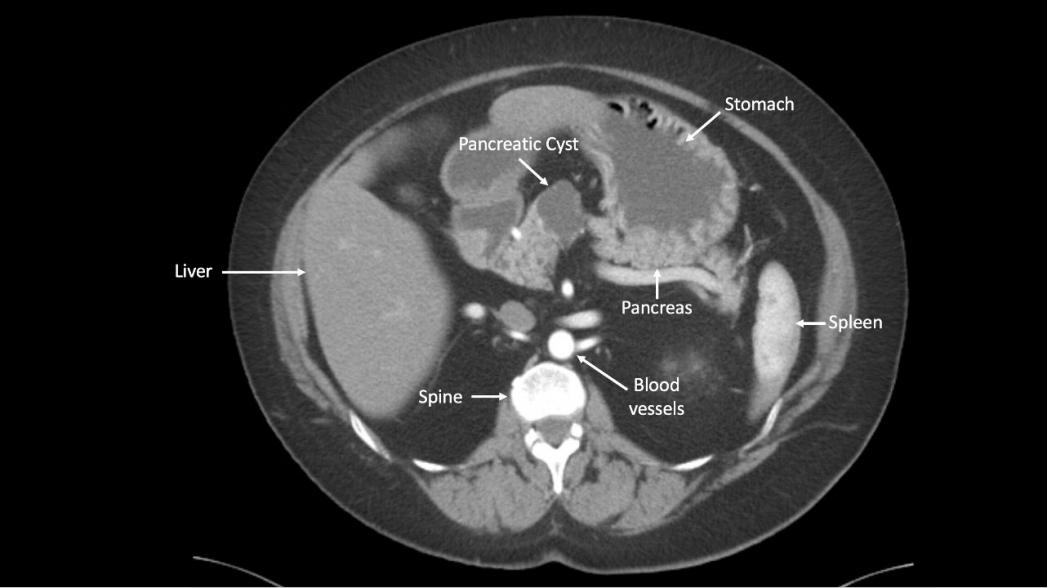

Американские исследователи из онкологического центра Киммеля больницы Джона Хопкинса разработали новый компьютерный и биомолекулярный инструмент, получивший название CompCyst, который может идентифицировать предраковые кисты поджелудочной железы. Технология предоставляет новый метод для надежной идентификации онкологических кист среди других подобных образований, которые не являются причиной рака.

Кисты поджелудочной железы являются обычным явлением и образуются у многих людей, только в США за год такие образования появляются у 800 тыс. пациентов. Лишь небольшая часть этих кист в итоге вызывает рак, но до сих пор было трудно определить, будет ли данная киста раковой, из-за ограничений текущих клинических и визуальных тестов. Это означает, что почти все люди с диагнозом "киста" отслеживаются в течение длительного времени, и многие могут подвергаться хирургическому удалению кисты, что приводит к дополнительным расходам и нагрузкам на систему здравоохранения и повышает риск смертности для пациентов. Для решения этой проблемы исследователи разработали CompCyst.

CompCyst - это схема классификации, основанная на логике булевых множеств, которая использует информацию молекулярных тестов и данные визуализации для определения того, может ли киста поджелудочной железы привести в итоге к раку. Данные, полученные с помощью этой системы, сравнивались с гистопатологией - золотым стандартом для выявления кист поджелудочной железы и инвазивным методом, который не используется в клинической практике на регулярной основе.